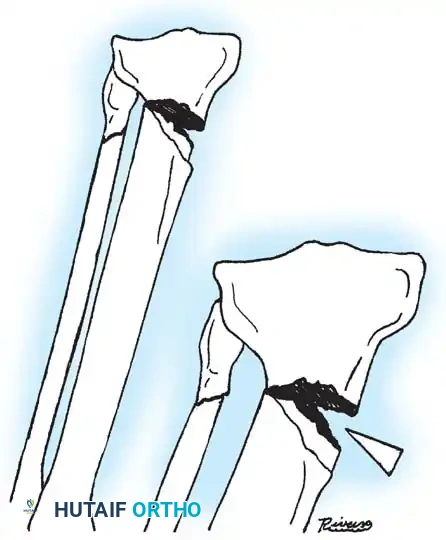

Fig. 33-173: Salter-Harris type I and II fractures with posterior displacement of the tibial shaft may severely injure the popliteal artery.

2. Vascular Proximity: The popliteal artery is firmly tethered posteriorly by the fibrous arch of the soleus muscle. When the proximal tibial shaft is displaced posteriorly in Salter-Harris Type I and II fractures, the artery is stretched over the sharp metaphyseal ridge, leading to intimal tearing, thrombosis, or complete transection.

- Type I and II Fractures: Most can be managed with closed reduction and a bent-knee cast. However, posterior displacement requires meticulous reduction to relieve arterial tension. Unacceptable angulation must be corrected; malunion in older children will not remodel sufficiently.

- Type III Fractures: These present in two distinct patterns:

- An intra-articular fracture analogous to an adult tibial plateau fracture.

- A fracture propagating through the tibial tuberosity physis, extending proximally across the epiphysis and into the knee joint.